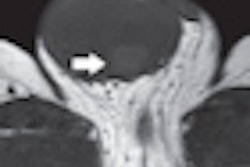

| Transverse SPECT/CT image (C) shows two sentinel nodes displayed in yellow. CT image (D) shows medial sentinel node corresponding to small lymph node ventral to area between aorta and cava, whereas lateral node is in area ventral to psoas muscle (circles). |

A review of the images found that lymphoscintigraphy in combination with SPECT/CT showed lymphatic drainage in all 10 patients (100%), and a total of 21 sentinel nodes were preoperatively identified. SPECT/CT also accurately located the sentinel nodes and provided anatomic reference points to plan the laparoscopy in all patients.